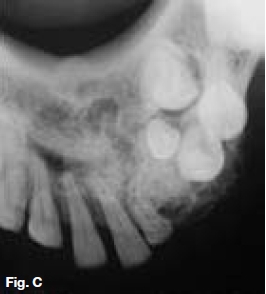

A 30-year old female presented with a swelling extending between 35 and 43, which had grown over the past ten months (Figs.A,B,C), with intermittent pain. Figures D,E,F show a similar case in a 15 year old male patient. Describe the radiological features and list your differential diagnosis.

The cropped pantomograph (Fig.B) shows a multilocular radiolucency of an expansive tumour containing varying calcifications. Figures D&E show a well demarcated multilocular lesion in the body/ramus region of the left mandible, with two displaced molar teeth, resorption of the roots of 34 and 35 and tooth-like calcifications at the borders of the lesion. The coronal T2 MRI image (Fig.F) shows a multilocular hyper-intense lesion, with no discernible calcifications. Diagnosis: the rare tumour, odonto-ameloblastoma (OA), first reported by Kemper and Root (1944). Shafer ef al (1983) described this as an odontogenic neoplasm of mixed tissue origin, consistent with both ameloblastoma and odontoma. Histologically, a typical ameloblastoma component whilst the odontoma element may be either compound or complex. Shafer et al (1983) emphasized that this is one neoplastic process with relatively highly undifferentiated tissues. Occurring most commonly in the second decade of life, it may vary in size. Smaller lesions occur between the teeth, confined to the alveolar bone between the crest of the ridge and the teeth apices (Figs. A,B&C). Buccal expansion of the cortex is common, even for smaller lesions. The odontoma component presents various stages of development, early lesions being radiolucent with radiopaque flecks. More mature lesions are better developed odontoma, resembling teeth or as a nonspecific complex odontoma mass. Importantly, this is an aggressive tumour, treated precisely as an ameloblastoma. The differential diagnosis should include: ameloblastic fibro-odontoma, Pinborg tumour, calcifying odontogenic cyst and adenomatoid odontogenic tumour.